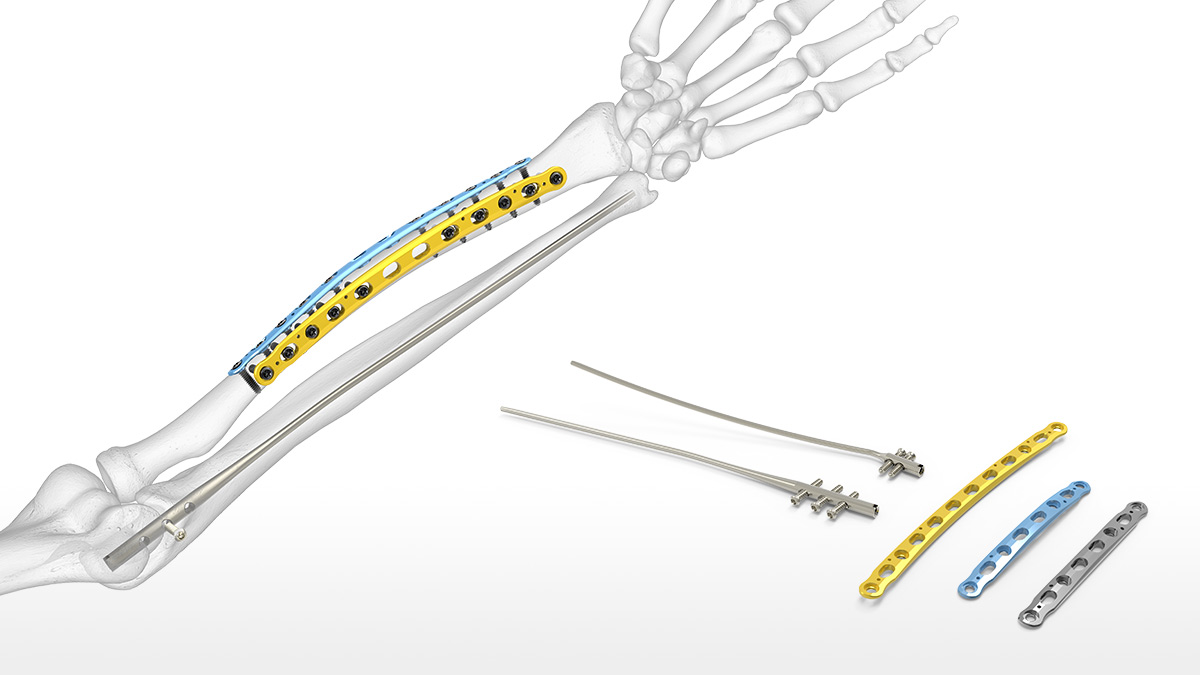

Product id: Forearm fracture on sale

Adult Forearm Fractures OrthoInfo AAOS on sale, Forearm Fracture Orthopaedic Trauma Association OTA on sale, Radius and Ulnar Shaft Fractures Trauma Orthobullets on sale, Adult Forearm Fractures OrthoInfo AAOS on sale, Pediatric Both Bone Forearm Fractures Commack NY Forearm on sale, Forearm Fracture Brandon P. Donnelly MD on sale, Forearm fracture Radiology Reference Article Radiopaedia on sale, Both Bone Forearm Fracture Pediatric Pediatrics Orthobullets on sale, Forearm Fracture Orthopaedic Trauma Association OTA on sale, Ten year old male child who sustained right both bone unstable on sale, Forearm Fractures in Children Types and Treatments OrthoInfo on sale, Adult Forearm Fractures Physioflow PT Physical Therapy on sale, Forearm Fractures May Signal Intimate Partner Violence Imaging on sale, Let s play Forearm fractures Radiology Key on sale, ICE 001 Forearm injury LITFL ICE Clinical Cases on sale, Forearm Fracture Management in the ED Practice Essentials on sale, Forearm Fractures Core EM on sale, Management of pediatric forearm fractures what is the best on sale, Both bone forearm fracture with rotation Radiology Case on sale, Fore Arm Fracture Drsinghphysiocare on sale, Broken Arm Fractured Arm Symptoms Treatment Recovery on sale, Childhood Forearm Breaks Resulting from Mild Trauma May Indicate on sale, Forearm Fractures Dr Carrie Kollias MD FRCSC FRACS Orthopaedic on sale, Treatment of nonunion after forearm fractures in children a on sale, Forearm fracture WikEM on sale, Ulna Fracture Treatment Dallas Frisco Prosper Wylie SPORT on sale, Forearm fracture on sale, Forearm Radius and Ulna Fractures Reno Orthopedic Center on sale, Pediatric Forearm Fracture Denver CO Elbow Fracture Aurora on sale, Kid s Forearm Fracture Raleigh Hand Surgery Joseph J on sale, Greenstick Fractures of the mid Radial and Ulnar Diaphysis with on sale, Forearm Fracture Brandon P. Donnelly MD on sale, Forearm Fractures The Bone School on sale, Imaging results of the patient s right forearm fracture at initial on sale, Forearm Fracture Solutions Acumed on sale.

Adult Forearm Fractures OrthoInfo AAOS on sale, Forearm Fracture Orthopaedic Trauma Association OTA on sale, Radius and Ulnar Shaft Fractures Trauma Orthobullets on sale, Adult Forearm Fractures OrthoInfo AAOS on sale, Pediatric Both Bone Forearm Fractures Commack NY Forearm on sale, Forearm Fracture Brandon P. Donnelly MD on sale, Forearm fracture Radiology Reference Article Radiopaedia on sale, Both Bone Forearm Fracture Pediatric Pediatrics Orthobullets on sale, Forearm Fracture Orthopaedic Trauma Association OTA on sale, Ten year old male child who sustained right both bone unstable on sale, Forearm Fractures in Children Types and Treatments OrthoInfo on sale, Adult Forearm Fractures Physioflow PT Physical Therapy on sale, Forearm Fractures May Signal Intimate Partner Violence Imaging on sale, Let s play Forearm fractures Radiology Key on sale, ICE 001 Forearm injury LITFL ICE Clinical Cases on sale, Forearm Fracture Management in the ED Practice Essentials on sale, Forearm Fractures Core EM on sale, Management of pediatric forearm fractures what is the best on sale, Both bone forearm fracture with rotation Radiology Case on sale, Fore Arm Fracture Drsinghphysiocare on sale, Broken Arm Fractured Arm Symptoms Treatment Recovery on sale, Childhood Forearm Breaks Resulting from Mild Trauma May Indicate on sale, Forearm Fractures Dr Carrie Kollias MD FRCSC FRACS Orthopaedic on sale, Treatment of nonunion after forearm fractures in children a on sale, Forearm fracture WikEM on sale, Ulna Fracture Treatment Dallas Frisco Prosper Wylie SPORT on sale, Forearm fracture on sale, Forearm Radius and Ulna Fractures Reno Orthopedic Center on sale, Pediatric Forearm Fracture Denver CO Elbow Fracture Aurora on sale, Kid s Forearm Fracture Raleigh Hand Surgery Joseph J on sale, Greenstick Fractures of the mid Radial and Ulnar Diaphysis with on sale, Forearm Fracture Brandon P. Donnelly MD on sale, Forearm Fractures The Bone School on sale, Imaging results of the patient s right forearm fracture at initial on sale, Forearm Fracture Solutions Acumed on sale.